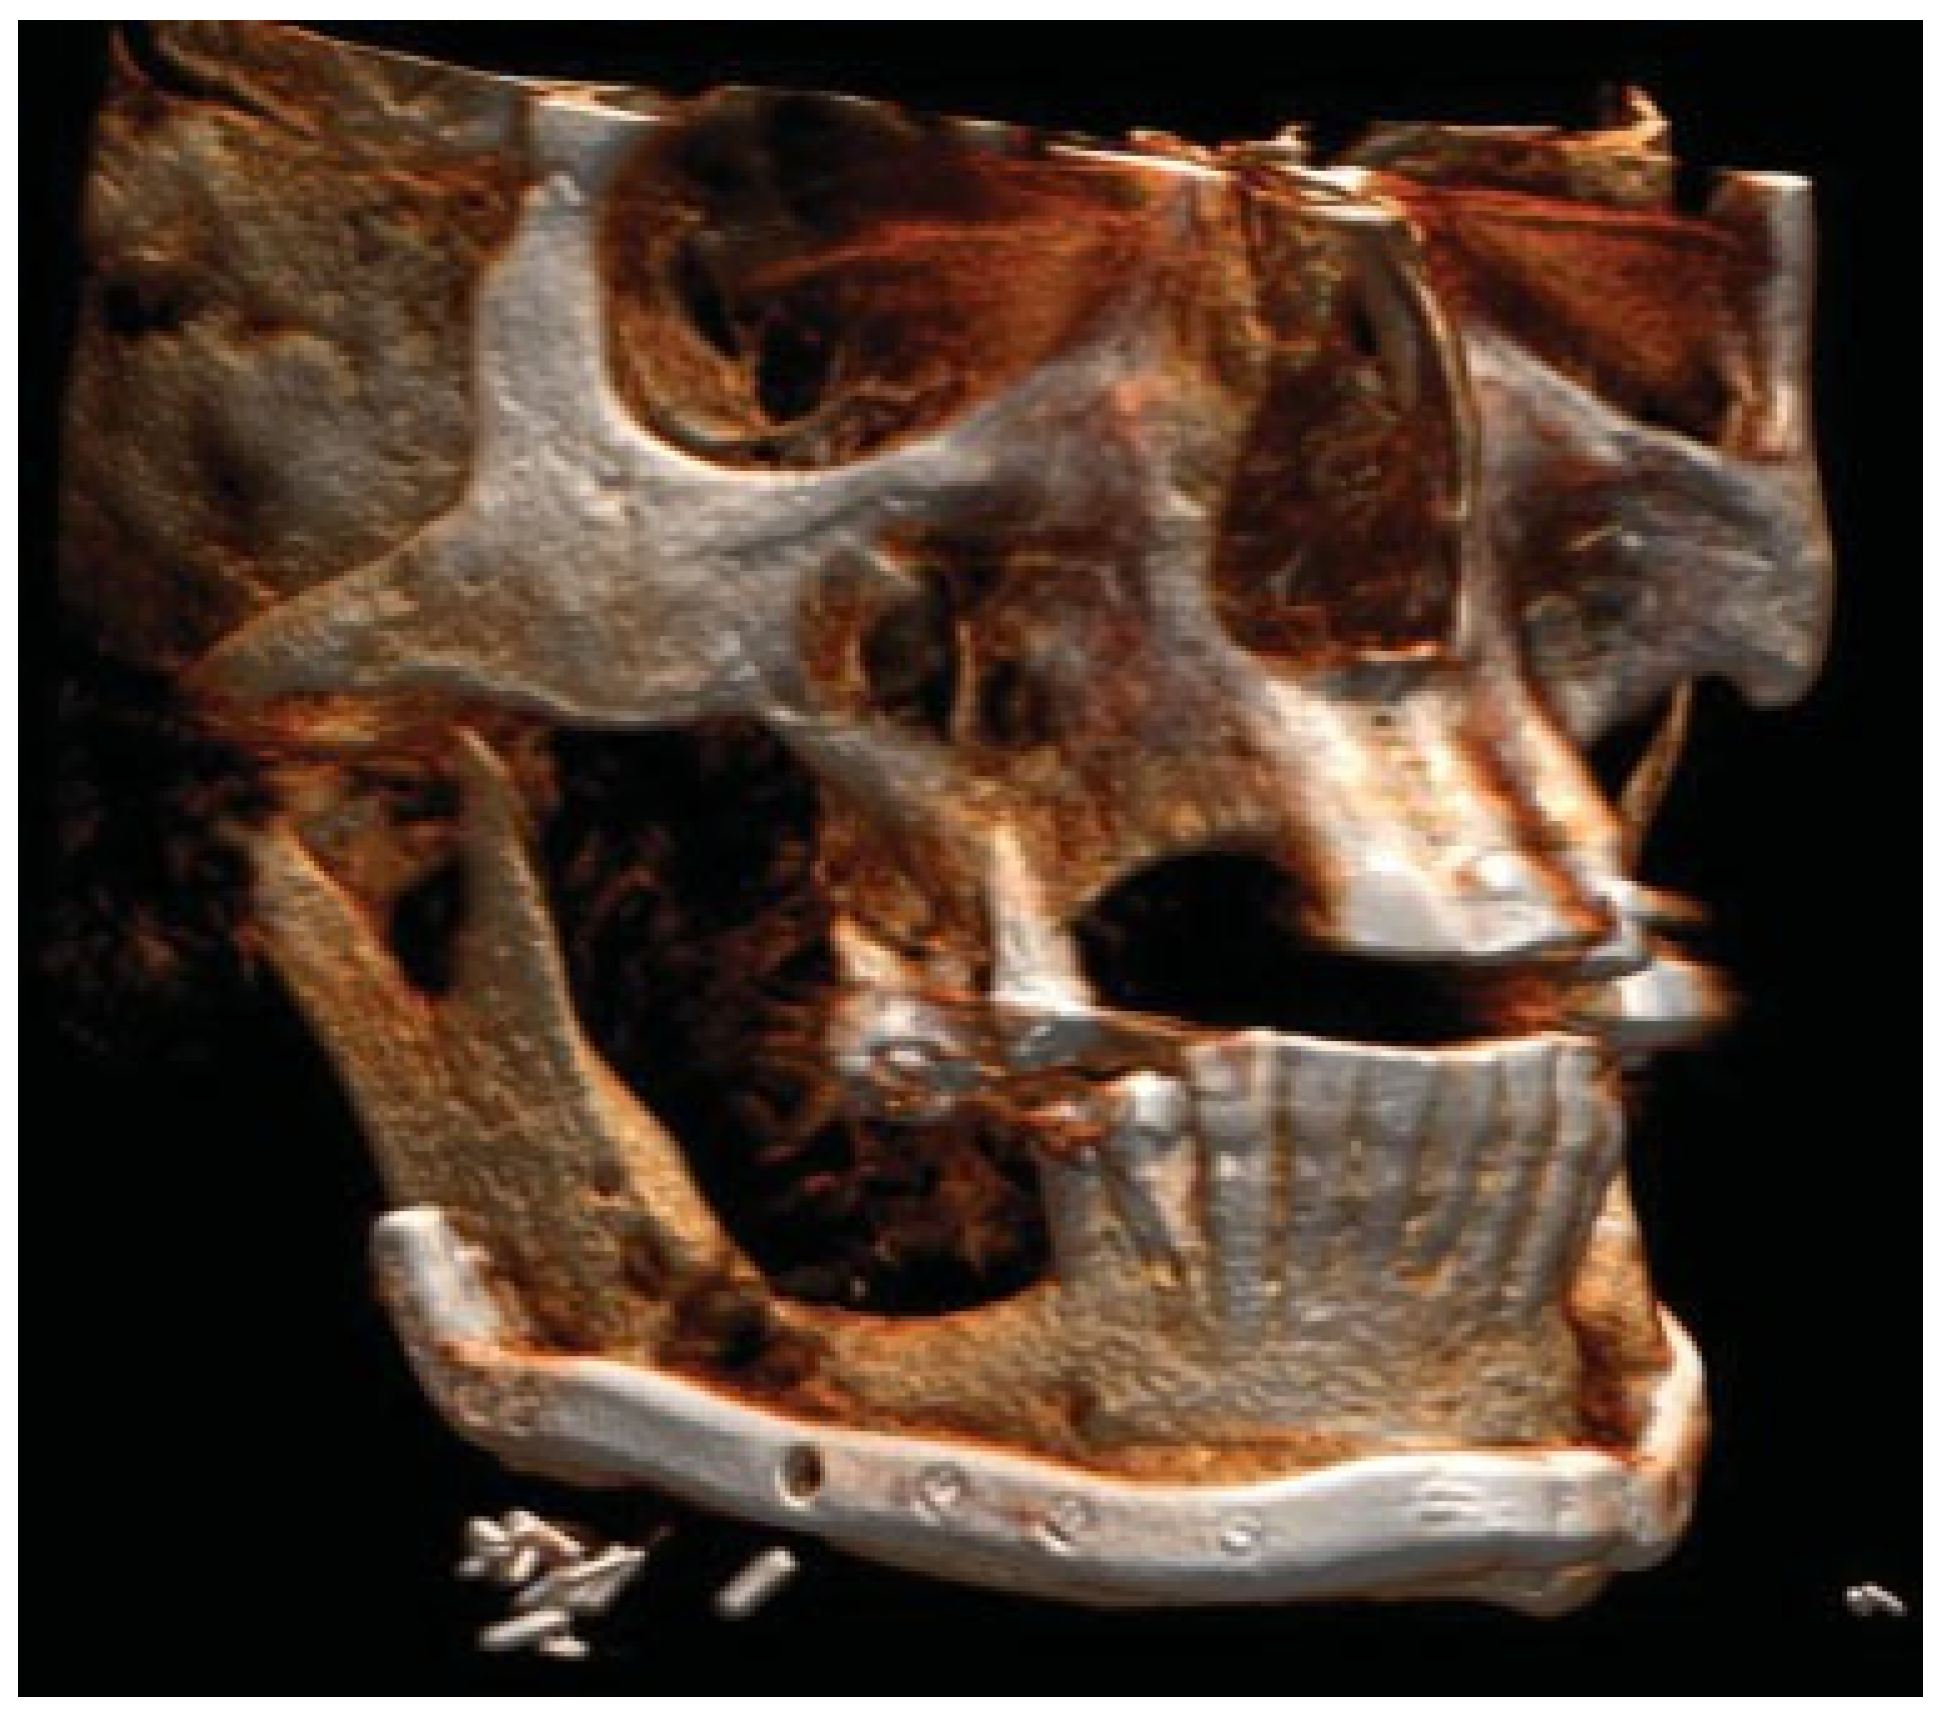

Figure 2.

Post-operative situation after bilateral intraoral plate fixation and placements of basal screws via trocar.

Figure 3.

Patient developed infections with oral mucosal fistulas in the fracture areas and an open bite. CBCT displays obvious anterior rotation of proximal segments and posterior rotation of the dentate part of mandible. Considerable muscle action creates new dislocation and is not counteracted by the inadequate osteosynthesis of the fractures.